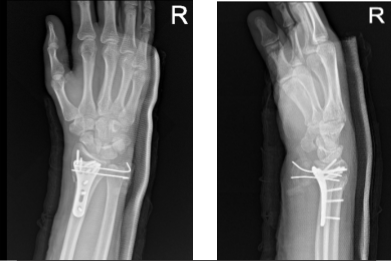

Two weeks post operative passed. Xray reviewed and showed fracture fragments appear in good position and alignment.

Right wrist X-ray 3 or more views-2nd week post operative